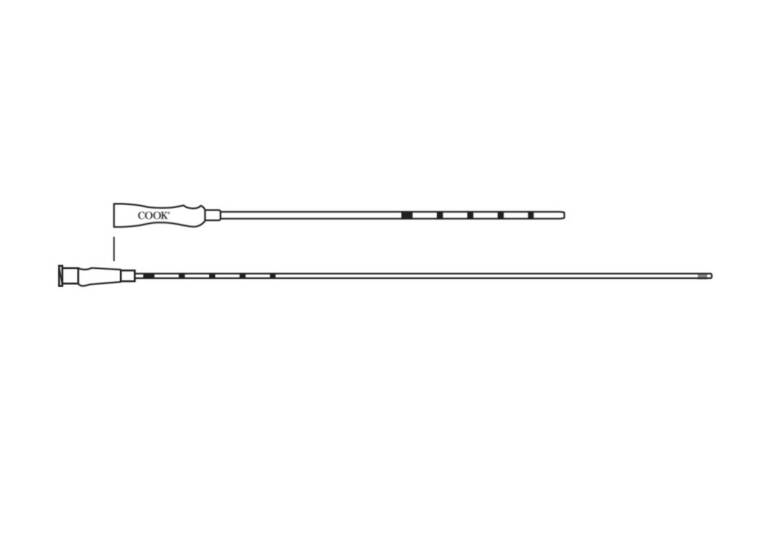

Cook® Soft-Pass Embryo Transfer Catheter Set

DESCRIPTION:

Used to place in vitro fertilized (IVF) embryos into the uterine cavity.

- The soft, flexible guide catheter is designed to facilitate placement of the set.

- Sets are available with transfer catheters that have an integrated stainless steel support cannula to aid catheter placement.